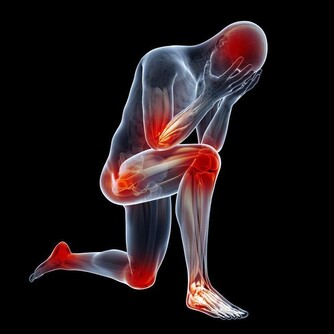

人們產生各種情緒很正常,但如果負面情緒持續時間過長,就會影響健康,

可因此引發抑鬱、焦慮等精神類疾病,甚至誘發多種器質性病變。教你找到壞情緒的根源,分分鐘化解它們。

大怒傷肝,過度憤怒可使肝氣橫逆上沖,出現面紅目赤、頭痛、頭暈的症狀。經常發火的人容易失眠、工作效率低、記憶力變差。

愛生悶氣的人容易肝氣不疏,還會連累脾胃,導致人們食慾不振、消化不良和腹瀉,在吃飯時與別人發生爭吵也會出現這種症狀。

肝氣鬱結還可能導致抑鬱情緒或內分泌紊亂,比如出現月經不調、皮膚長痘長斑等。

從西醫的角度來看,人生氣時,體內會分泌一種叫“兒茶酚胺”的物質,作用於中樞神經系統,使血糖升高、脂肪酸分解加強,血液和肝細胞內的毒素相應增加,堆積於肝,從而損傷肝臟。